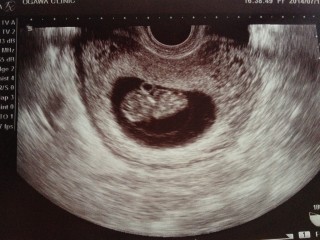

初めての妊娠です。エコーで赤ちゃんが動いてるのを見た時、すごく嬉しかったです。次の検診まで何日かありますが、成長している姿が見れる事を期待しています。

今回初めて手足がはっきり見えました!くねくねと動いているのがあまりにも可愛くて笑ってしまいました(^O^)次回も楽しみです♪

手足をピクピク動かしてました☆

これからも赤ちゃんの成長が

楽しみです(*^^*)